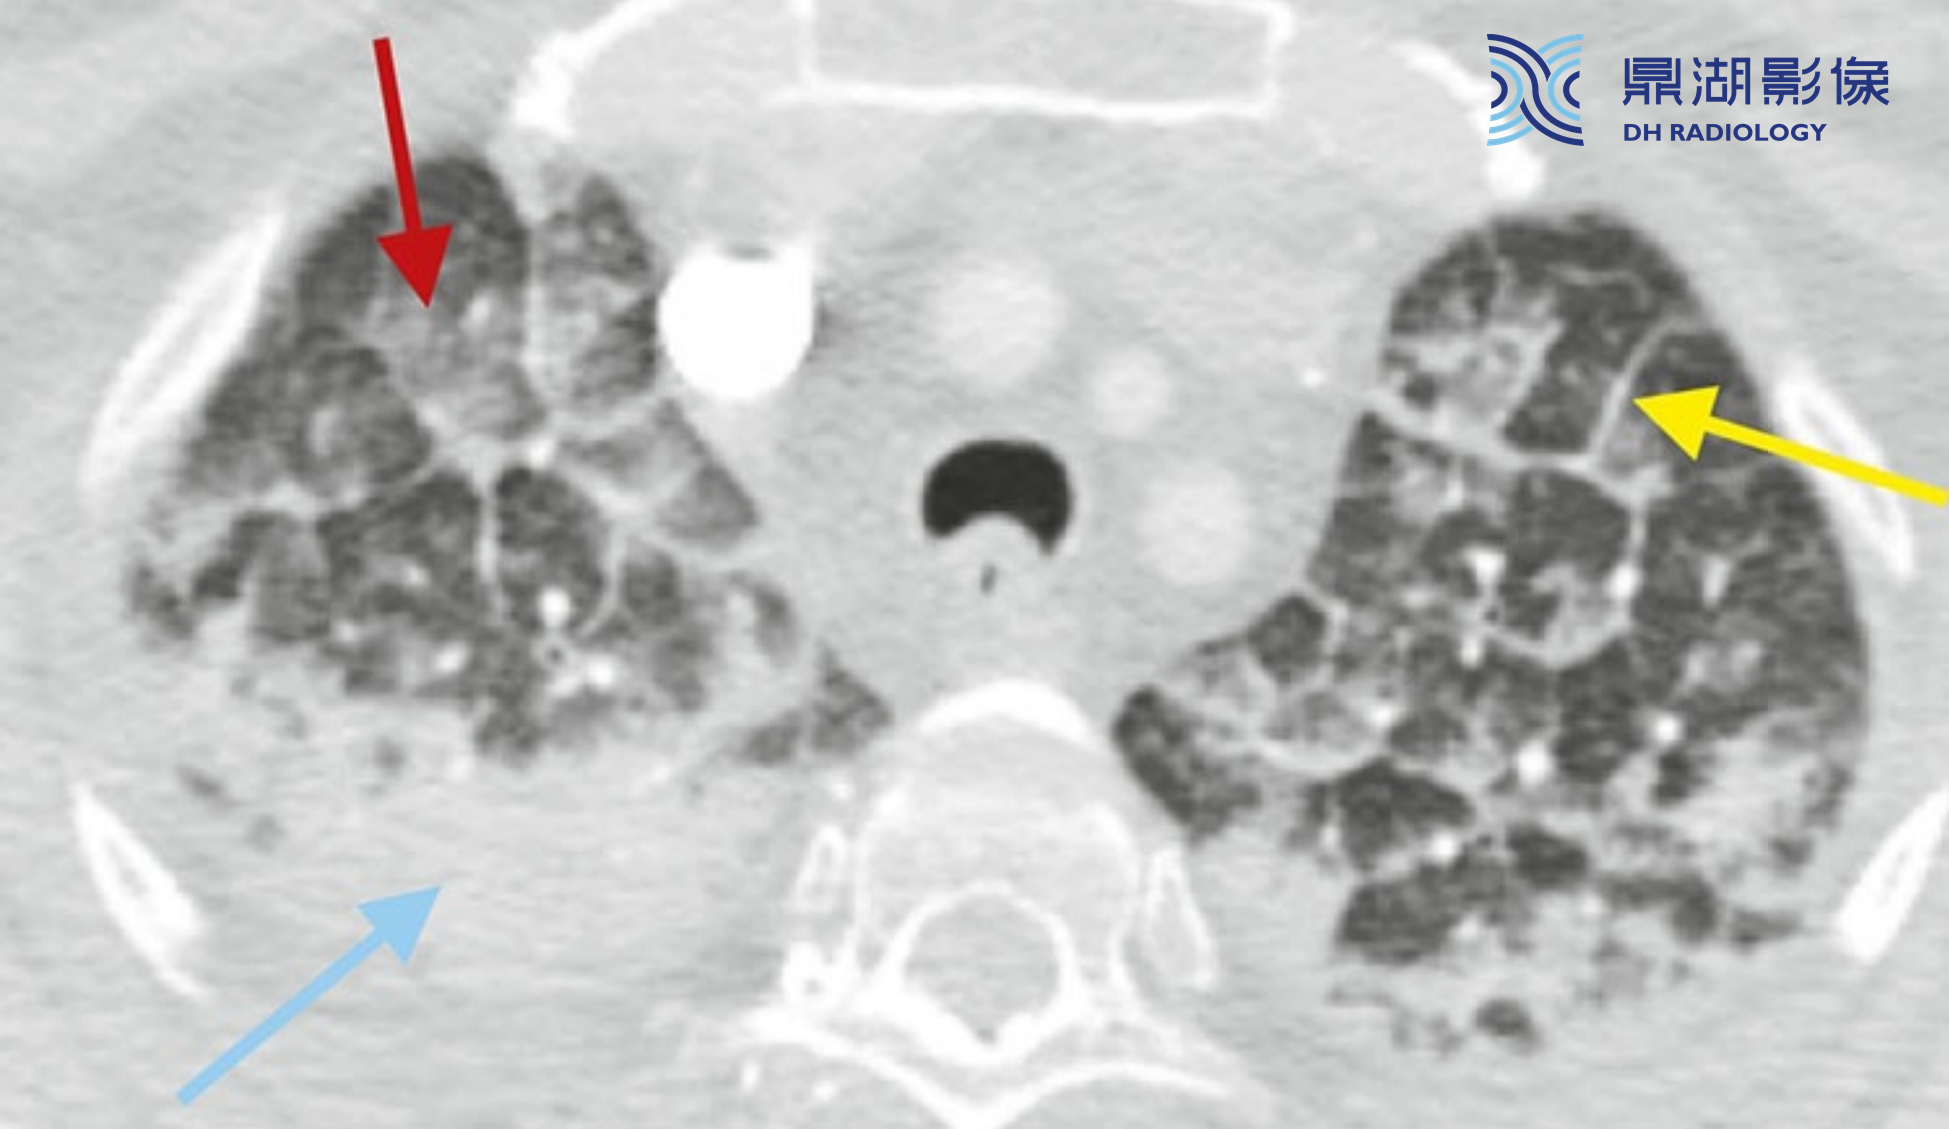

4e4573356b881b39ebd9f3c63d198e08.png

间质性和肺泡性肺水肿的典型表现。小叶间隔平滑增厚(黄箭)是间质性肺水肿的一种表现。另外,可见双侧散在的GGO(红箭) 和实变(蓝箭),这是肺泡性肺水肿的表现。间质性和肺泡性肺水肿的异常表现常同时存在。